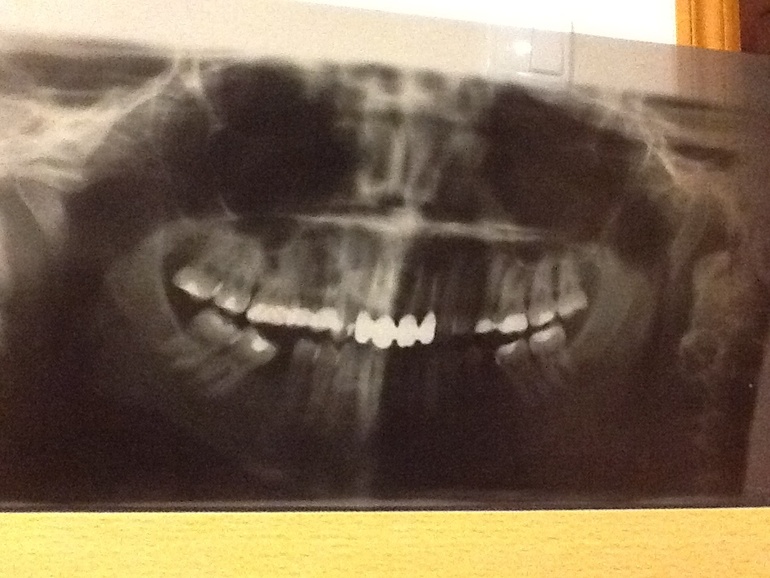

Вот фото светлее интересует справа вверху 5 6 зуб

Я уже писала,что почле лечения 10 зубов,через какое то время начали ныть верхни зубы с правой стороны.Они именно ныли,не сильно болели.В этот понедельник я съездила к лору,проверили все чисто.Сделала ортопонтонограмму,сверху есть воспаление небольшое,решили пока ничего не трогать-третий день пью ксифокам,становится лучше(но зубы все равно побаливают).Меня теперь страшит другое,болит нижняя челюсть почти вся.Почему?

Фото темновато,но справа вверху видно 5 и 6 зуб

Пожалуйста, сделайте более четкую и светлую копию снимка. Не смогу по предложенному ответить на Ваш вопрос.